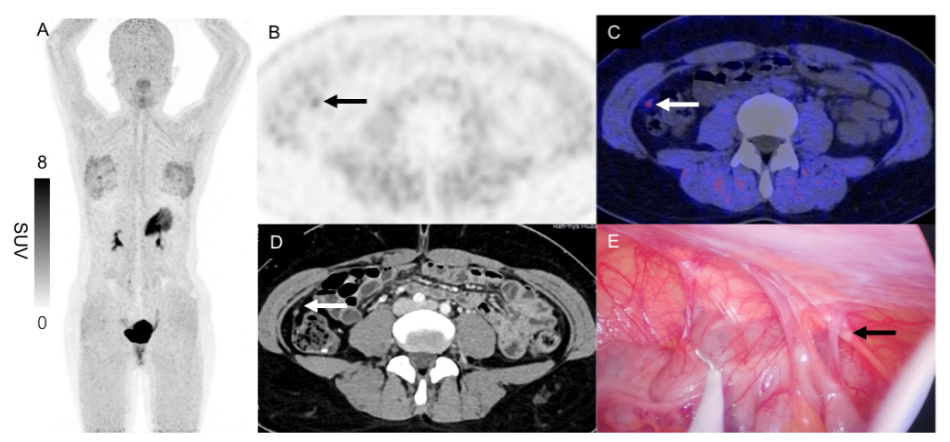

2例典型病例共同证明了68Ga-FAPI-04 PET/CT在检查进展期胃癌OPM中的独特价值,见图1和图2。

图2 1例24岁女性胃体低分化腺癌患者接受68Ga-FAPI-04 PET/CT检查显示:除原发肿瘤外腹部未见明显异常示踪剂摄取(A),轴位图像显示右结肠旁沟存在一个细微摄取灶(B、C,箭头所示,SUV最大值为1.71)。增强CT图像可见该部位强化结节,但初次诊断时被漏诊(D,箭头所示)。后续术前腹腔镜检查最终证实为OPM(E:箭头所示)